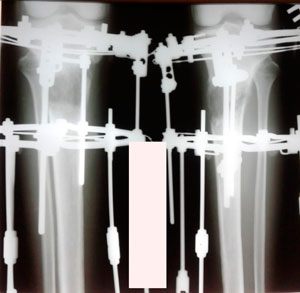

рентген в процессе удлинения

Процесс удлинения

Высший пилотаж pozdravlyau

Запомните: удлинять могут единицы во всём Мире

на фиксации

хотели удлиняться на 2 см, переиграли на 5 см debil